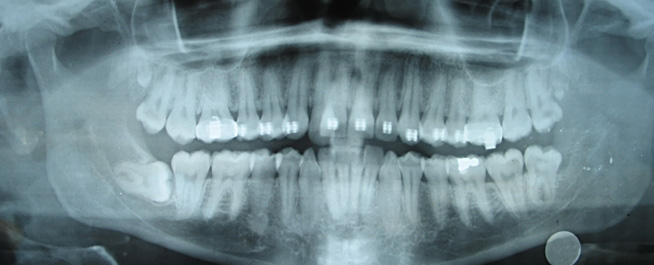

At Comfort Family Dental we pride ourselves on having the latest digital x-ray technology, which allows faster and safer service to our patients. Approximately 50% less radiation is used in every x-ray taken in our office. Our digital sensors can show us much more detail then standard film x-rays. Your x-rays are displayed on large screen flat panel television to let us show you any problems your teeth may have.